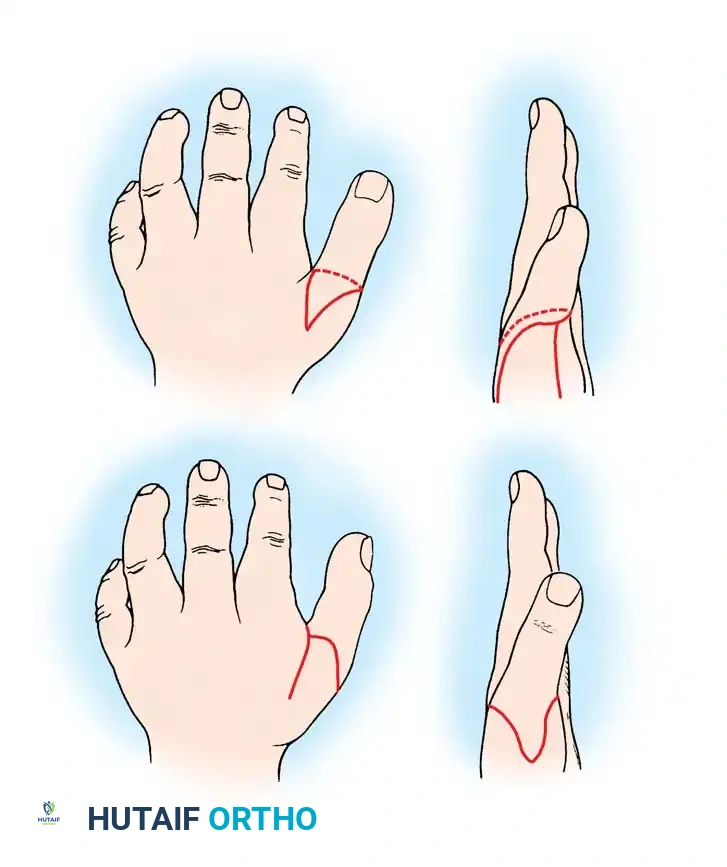

A newborn presenting with a transverse deficiency typically exhibits a slightly bulbous, well-padded stump. In more distal deficiencies, rudimentary, vestigial digital "nubbins" are frequently observed.

Fig. 76-2 Failure of formation (digital nubbins). The presence of functional wrist motion allows the limb to be used effectively as an assisting hand.

Hypoplasia of the more proximal musculature is a key clinical finding that helps differentiate true transverse deficiencies from amputations caused by congenital constriction band syndrome (amniotic band sequence). In the most common presentation—the upper forearm amputation—the forearm is usually no more than 7 cm long at birth and will reach a maximum length of approximately 10 cm by skeletal maturity.

In midcarpal amputations (the second most frequent level), the rudimentary digital remnants are almost always nonfunctional. However, because the radiocarpal joint is preserved, pronation and supination are usually possible, providing a highly functional assisting limb. Cognitive development and intelligence in these children are generally normal.